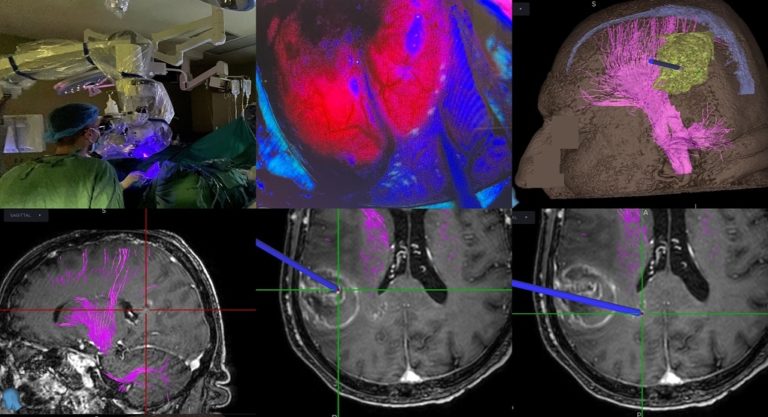

Η χρήση του 5-αμινολεβουλινικού οξέος επιτρέπει τον φθορισμό και αναγνώριση του όγκου διεγχειρητικά, με τη χρήση ειδικού τύπου μικροσκοπίου που διαθέτει η Νευροχειρουργική Κλινική. Έτσι μπορεί να γίνει αναγνώριση και πιο εκτεταμένη εξαίρεση του νεοπλασματικού ιστού, κάτι που έχει αποδειχθεί ότι αυξάνει την επιβίωση σε ασθενείς με υψηλής κακοήθειας γλοιώματα εγκεφάλου.

Επιπλέον, έγινε διεγχειρητική χρήση νευροπλοηγού, που διέθετε αλγόριθμο νέας τεχνολογίας για δεσμιδογραφία, κάτι που επιτρέπει την χαρτογράφηση σημαντικών οδών του εγκεφάλου και επομένως την επιλογή της κατάλληλης χειρουργικής προσπέλασης, με σκοπό την αποφυγή μόνιμου νευρολογικού ελλείμματος μετεγχειρητικά.